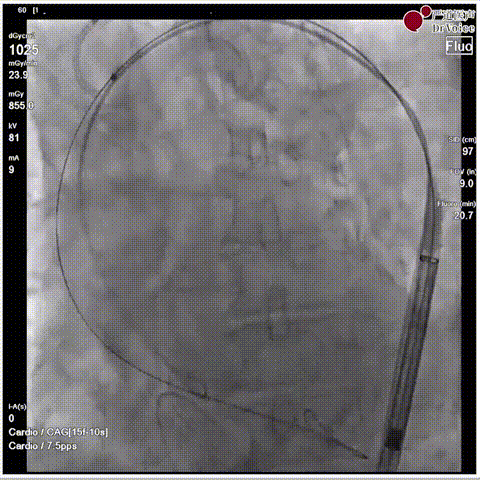

手术瓣膜释放后造影(4例)

病例一

病例二

病例三

病例四

快速过弓跨瓣(4例)